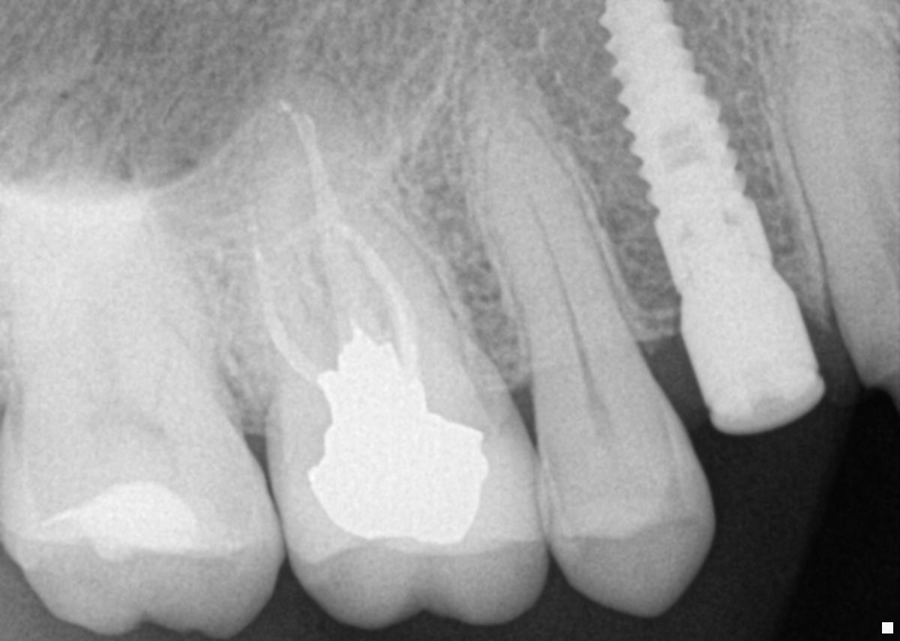

4. After surgery, several X-rays were taken to verify implant placement. Figure 7 shows accuracy to the guided placement for the implant in tooth #12 position (which mirrors the planning stage of Figure 4). Figure 8 shows the implant in tooth #8 position with healing abutment. Figure 9 shows the placement of the implant for tooth #5.

Fig. 9